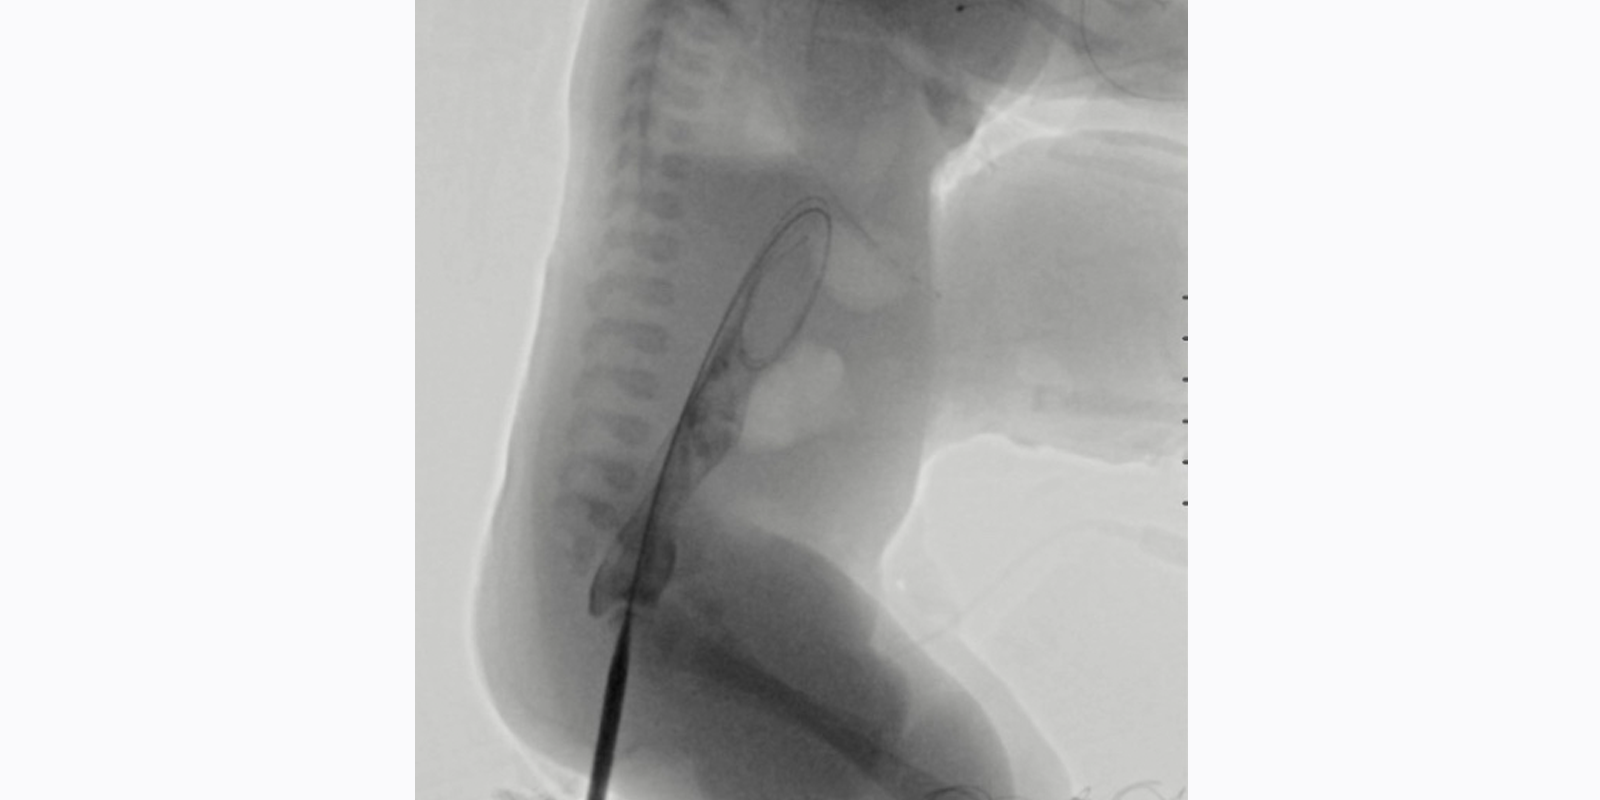

Inserting a stiff wire through the neo-anorectal tract allowed for serial dilation of the tract under fluoroscopic guidance. Source: NYU Langone Health.

3 of 4